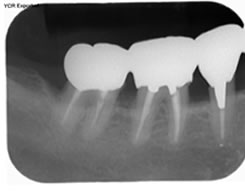

症例1

治療の特徴(患者T様)

平成13年7月7日 右下第一大臼歯頬側に膿瘍形成 著しい腫れ形成 著しい腫れ

- 男性33歳

- 平成14年11月9日 どうしても抜きたくないということで歯周外科処置する。

- その後H16から1~2カ月おきにメインテナンス。

- 平成16年6月11日 歯周治療により骨が出来てきています。

口の中から細菌を除去し、良好な環境を維持していくことによって歯周組織である歯槽骨や歯肉、歯根膜は生き生きとよみがえってきます。継続は力なりと申しますが根気良く治療を続けることで健康が回復し維持されます。

| 治療期間 | 4年7カ月 |